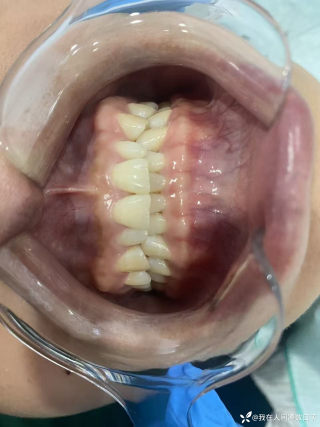

病例信息【患者信息】:男、16岁【主诉】:全身皮肤瘙痒伴皮疹10分钟【现病史及既往史】:10分钟前患者骑摩托车行驶途中,突感全身瘙痒,奇痒无比伴全身发热,心跳加快。急诊就诊,既往无类似病史,否认咽喉梗阻感、胸闷、气短、呼吸困难、恶心、呕吐、腹泻、乏力等不适。【检查】:血压:138/80mmHg,心率:116次/分,呼吸:21次/分。【临床诊断】:急性荨麻疹【治疗经过及结果】:给予吸氧、肌注扑尔敏1支,口服氯雷他定1片,静滴甲泼尼龙40mg后瘙痒明显减退,皮疹消失。病例讨论双手十指及双足未纹身,护士最后穿刺左手大拇指。